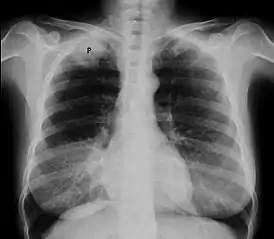

![]() Рентгенограмма органов грудной клетки, опухоль Панкоста (обозначена P, немелкоклеточная карцинома правого лёгкого) у курящей женщины 47 лет. | |

На КТ-скане визуализируется опухоль Панкоста у курящей женщины 47 лет (опухоль обозначена "Р", по гистологическим данным — немелкоклеточная карцинома правого лёгкого).